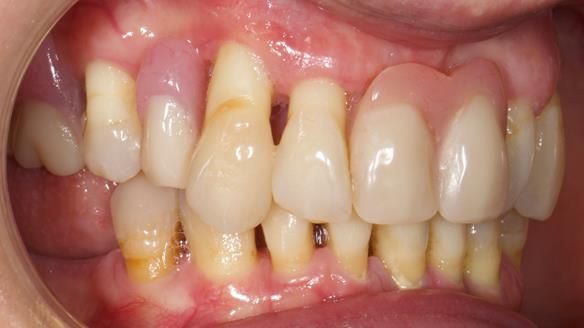

She had previously suffered from generalised periodontitis – stage IV, grade C, currently stable, with reduced attachment across the upper arch.

By the time she came to me, her periodontal condition was stable — but the aesthetics in the upper jaw were very poor.

Ultimately, she decided against dental implants:

- Her upper jaw had insufficient bone and would have required significant augmentation.

We provided her with an immediate upper denture (Mk 1), followed by a definitive metal-based upper denture (Mk 2). A lower removable partial denture was discussed, to be made only if needed once the upper treatment was complete. However, at review, this wasn’t necessary — Adnana had excellent neuromuscular control and function, even with a shortened dental arch (SDA).